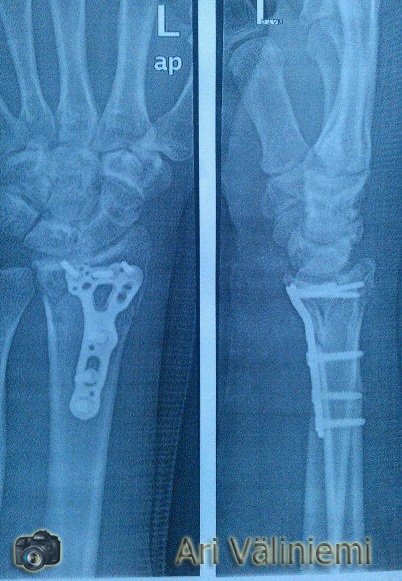

Myös pahoja loukkaantumisia mahtuu kuvioihin. Merkittävin 2012 kesällä Kurikassa pöytähyppyrin yli hypätty loikka katkaisi molemmat kädet alastulossa. Toinen käsi vahvistettiin titaanilla, kun luut oli pirstaloitunut sen verran pahasti. Toinen pysyi kipsillä kasassa.

Liikuntarajoitteiset ja osin hermovaurioiset kädet on nyt seuranani. Mutta ei se ainakaan vauhtia ole hidastanut!